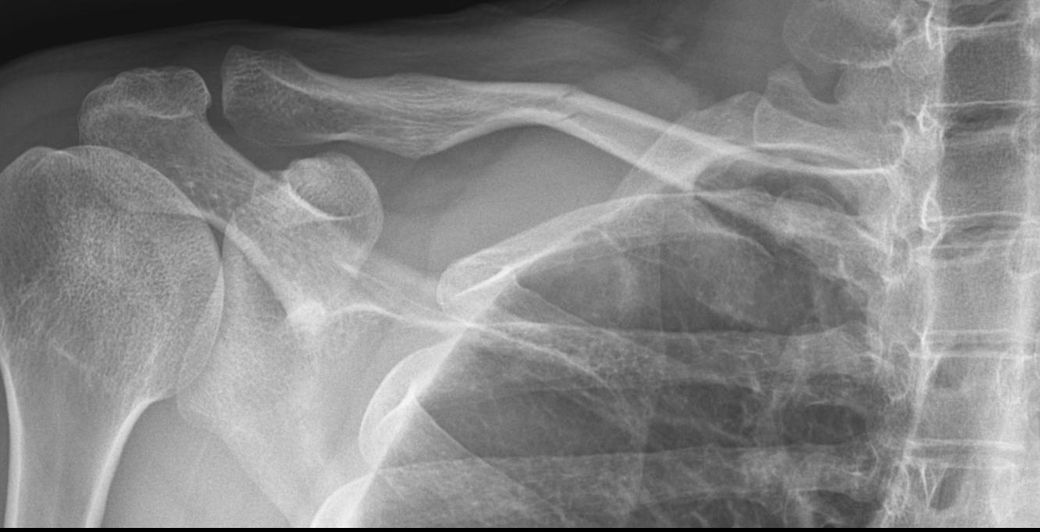

• 이미 정형외과에서 설명은 다 들으셨겠지만, 사진상으로는 쇄골 중간부 골절이며, 골편이 약간 겹치면서 단축이 동반된 형태로 보입니다. 쇄골은 이런 방식으로 골절되면 근육 견인 때문에 일부 겹침이 생기고, 그 결과 길이 단축이 발생하는 경우가 흔합니다.

회복 후 단축 가능성은 있습니다. 다만 대부분은 경미한 범위에서 발생하며, 일반적으로 5 mm에서 15 mm 정도가 흔한 범주입니다. 2 cm 이상 단축되는 경우는 상대적으로 드물고, 이 정도가 되면 기능적 문제나 수술적 치료를 고려하는 기준이 됩니다.

엑스레이 사진상 쇄골 중위부 골절이 확인되며 골절편이 서로 겹쳐있는 전위상태로 보입니다. 골절부위가 맞물리지 않고 어긋나서 붙을경우 뼈의 총 길이가 짧아지는 길이 단축이 발생할 가능성이 매우 높습니다. 현재 겹쳐진 정도로 보아 대략 1~2cm내외의 단축이 예상되나 정확한 수치가 측면 사진 등 추가 검사가 필요합니다. 보통 2cm 미만의 단축은 일상생활에 큰 지장은 없으나 웨이트 트레이닝 같은 고강도 운동시 어깨 회전근개의 힘 전달이나 외관상 비대칭이 느껴질수 있습니다. 단순 팔걸이를 선택할경우 부정유합의 위험이 있고 정확한 정렬과 같이 회복을 원하면 금속판 고정 수술을 고려해야 할 단계로 보입니다. 정형외과 전문의와 수술여부를 심도있게 상의하시길 바랍니다!

엑스레이사 쇄골(빗장뼈) 골절로 보이며, 특히 중간부 골절은 약간 겹치며 붙으면서 길이 단축이 생길 수 있습니다.

보존치료 시 보통 0.5~2cm 정도 단축이 흔하고, 심한 경우 2cm 이상도 드물게 발생합니다.

엑스레이상 어긋남은 없는 것으로 보이나 그렇다고 해서 완전히 안심하기는 어렵고 병원에서 처방해드린대로 잘 치료 받아보시면 좋을 것으로 생각됩니다.